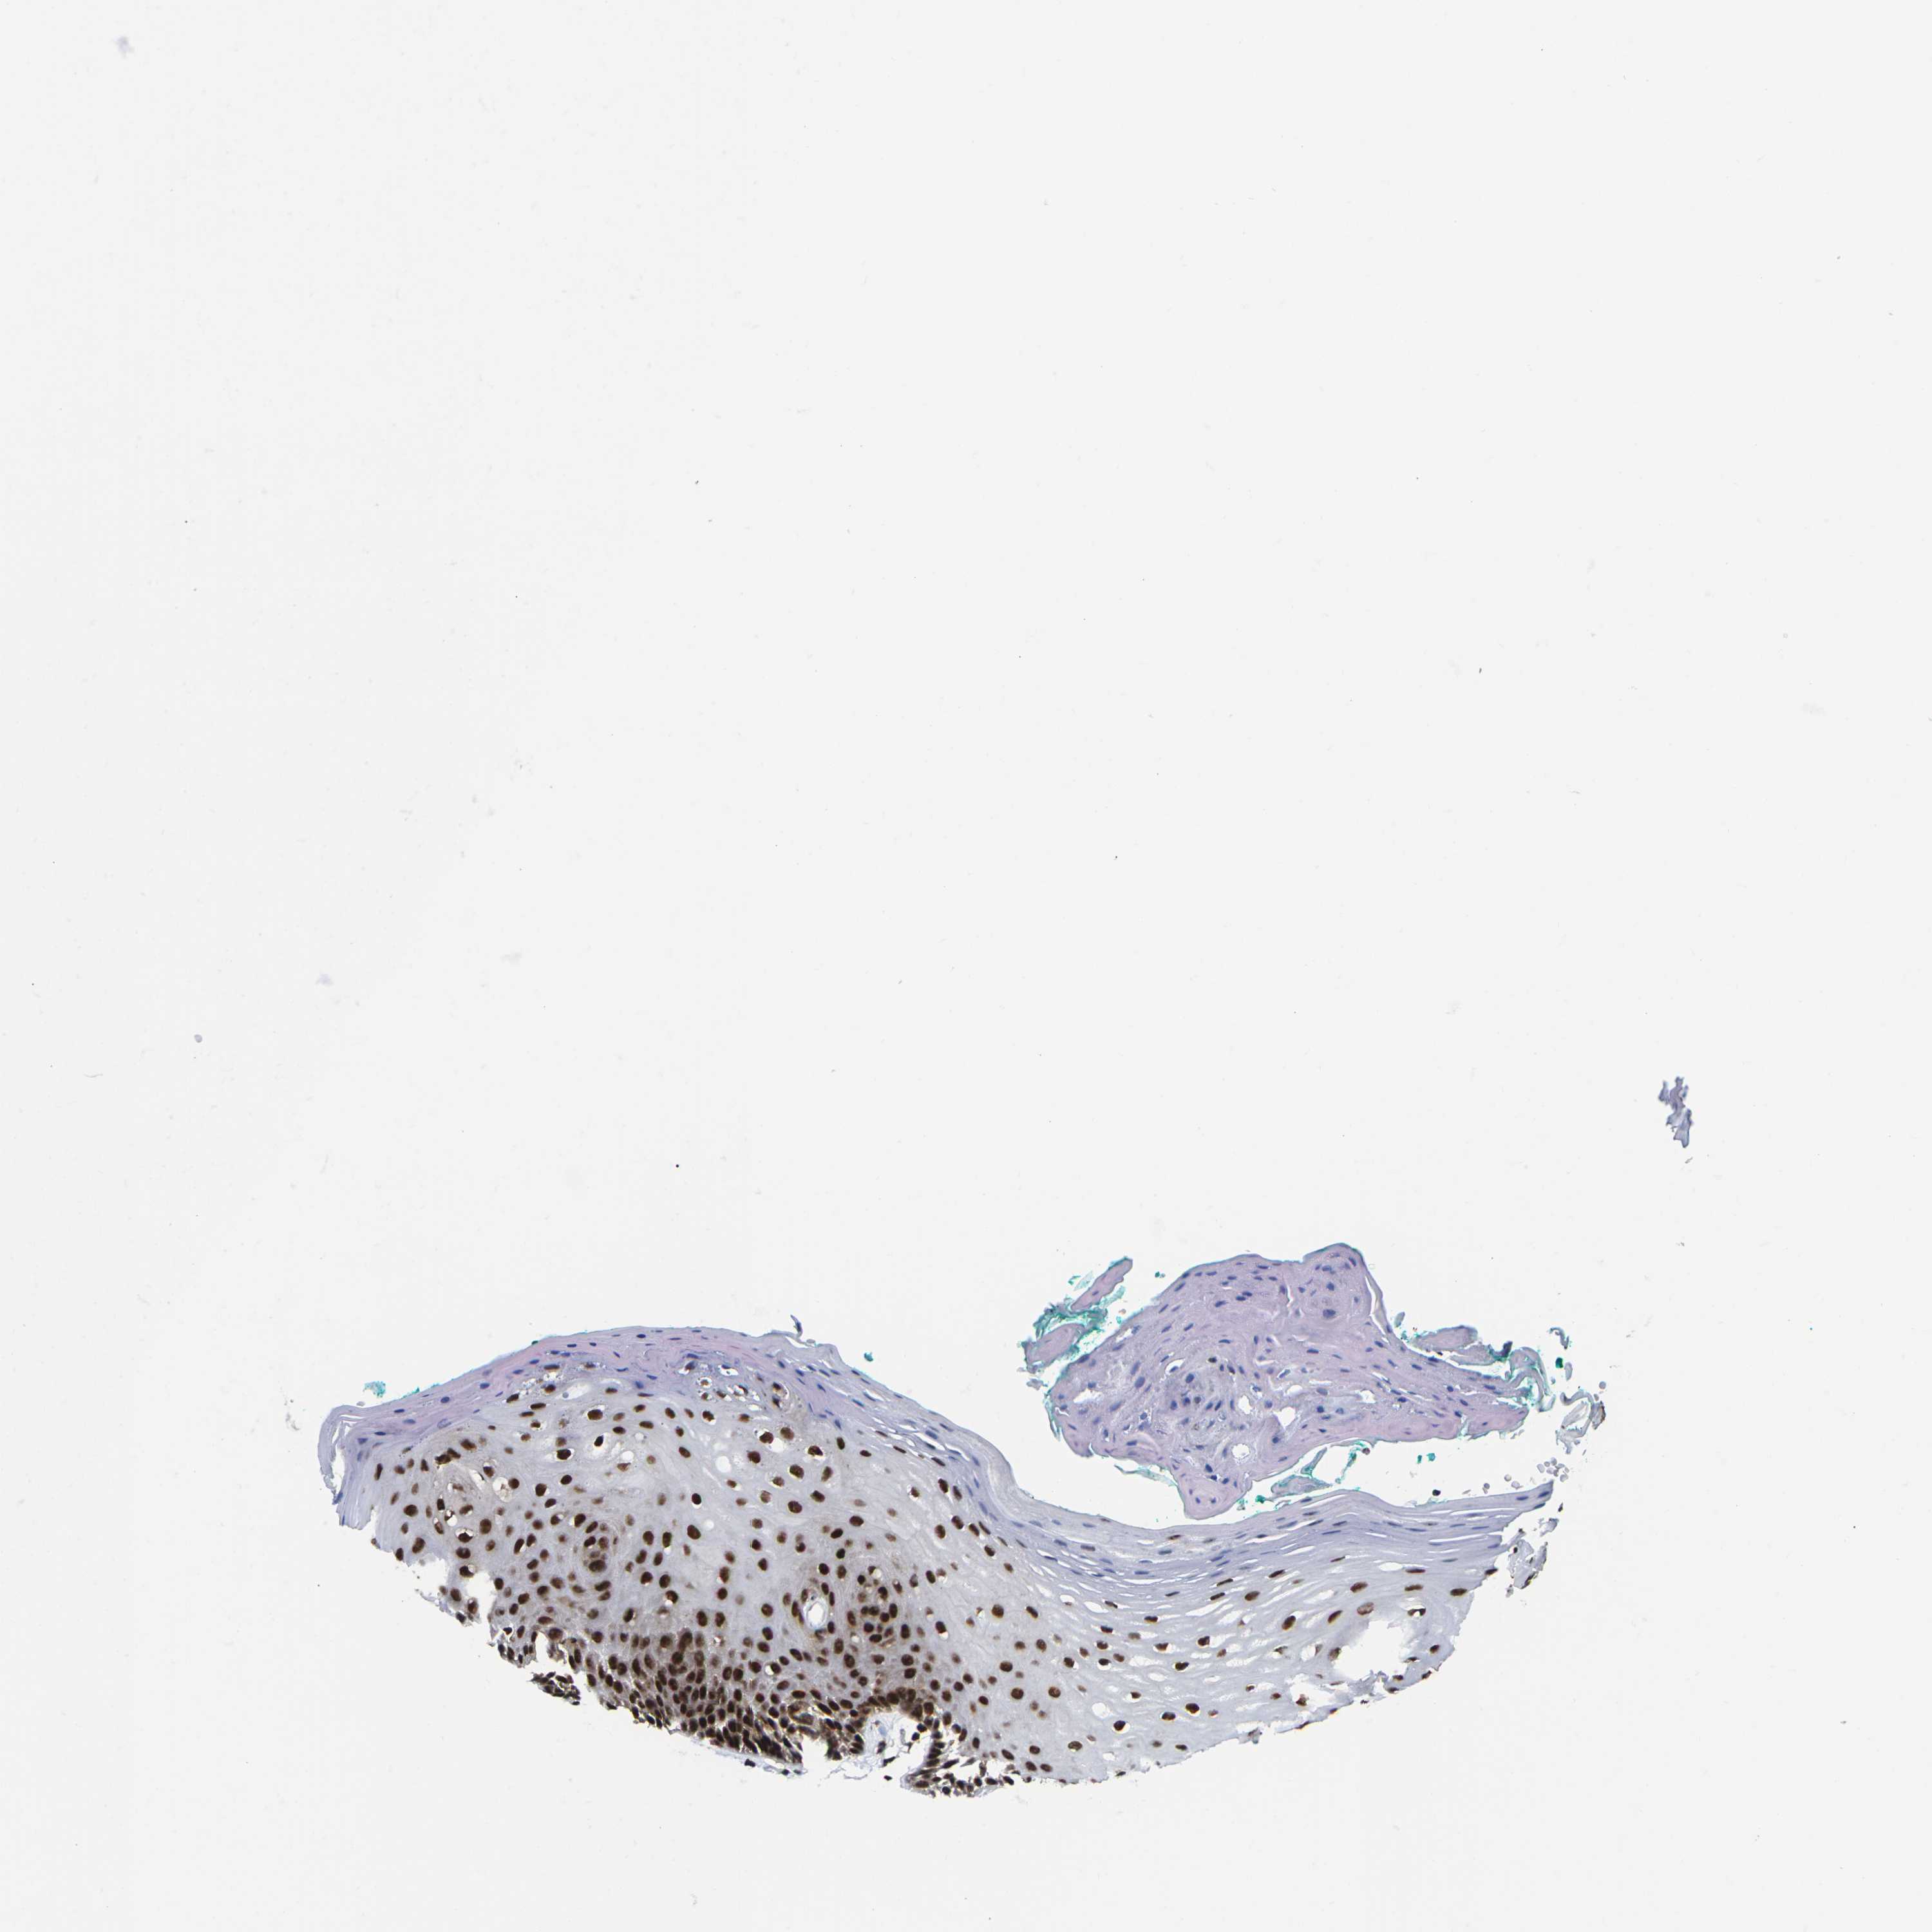

TISSUE PRIMARY DATA ORAL MUCOSA Show tissue menu

ORAL MUCOSA - Antibody stainingi

Antibody staining in the annotated cell types in the current human tissue is reported as not detected, low, medium, or high, based on conventional immunohistochemistry profiling in selected tissues. This score is based on the combination of the staining intensity and fraction of stained cells.

Each image is clickable and will lead to virtual microscopy that enables deeper exploration of all samples and also displays staining intensity scores, fraction scores and subcellular localization as well as patient and tissue information for each sample.

Antibody HPA043036Antibody HPA047754Antibody CAB015425

Squamous epithelial cells HighLowHigh